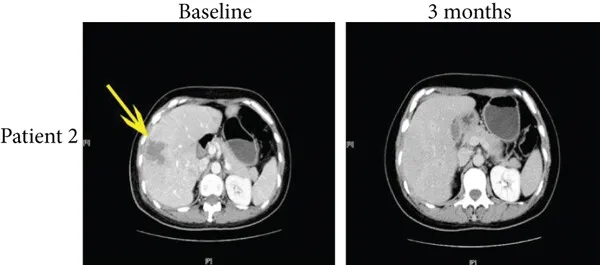

病例2是一位50岁患者,治疗前伴肝转移,患者在接受免疫治疗4个月后,多发性肝转移达到完全缓解(详见下图b,黄色箭头所示),PFS达10.9个月。

▲图源“J Immunol Res”,版权归原作者所有,如无意中侵犯了知识产权,请联系我们删除